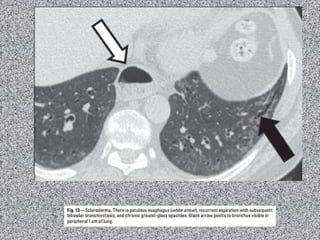

Bronquite crônica

Mulher de 20 anos, não tabagista com dispneia progressiva.

Linfangioleiomiomatose: mulher de 20 anos não tabagista.